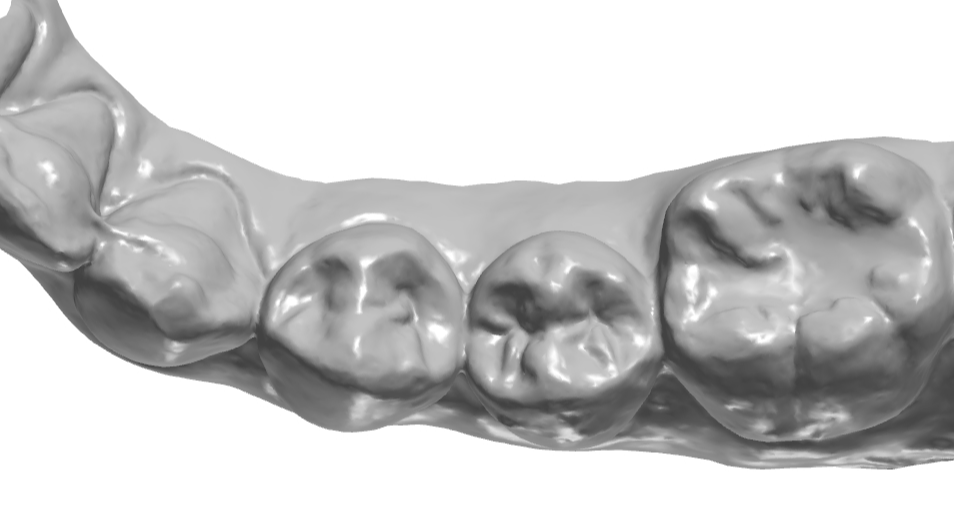

교합면에 형성되어 있는 엠브레져 체크.

설측 교합면쪽 엠브레져 체크.

교합면 확대.